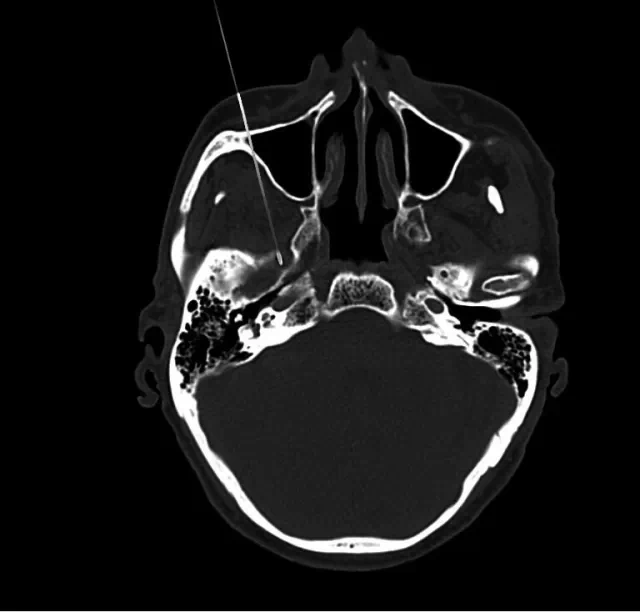

四川奥斯迪康骨医院治疗方法:CT引导射频热凝术

治疗原理:三叉神经为感觉神经,其中神经纤维(AA纤维和AB纤维)能耐受较高温度,而痛觉神经纤维不能耐高温,CT引导三叉神经热凝术选择破坏痛觉纤维,使患者疼痛治愈。

治疗优势:安全、疗效好、不易复发、无副作用、费用比手术治疗低、创伤小、痛苦小、治疗时间短。